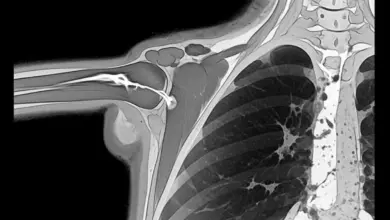

O exame avalia instabilidade, apreensão e padrão de dor, mas a confirmação costuma depender de ressonância magnética, muitas vezes com artrografia (contraste intra-articular), que melhora a visualização capsuloligamentar.